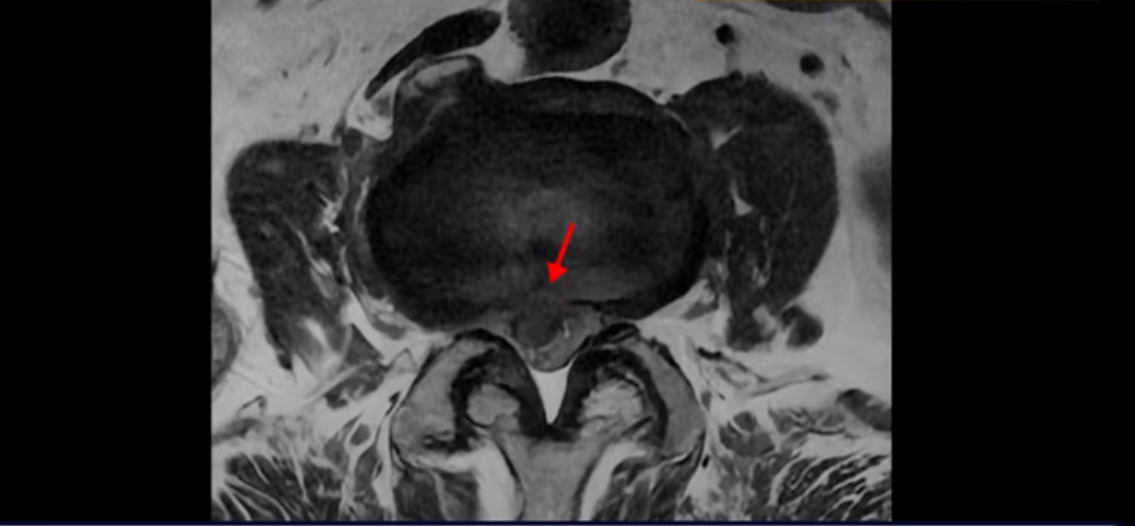

3번 4번에는 척추관협착과 디스크 탈출이 보이고

4번 5번에는 척추관협착과 심한 디스크 파열이 있습니다.

기립근의 지방화도 심합니다. 또 3번 4번 마디에서는 신경가지가 빠져나가는 추간공이 왼쪽, 오른쪽 모두 많이 좁아져 있습니다.

이런 이유로 이 환자분은 왼쪽 다리는 마비가 생겨 힘이 빠지고 오른쪽 다리에는 심한 방사통이 있어서 휠체어까지 타야 하는 상태가 되었습니다. 이렇게 심하니까 대학병원에서 여러 마디 나사를 박는 유합술을 권유 받으셨는데요.